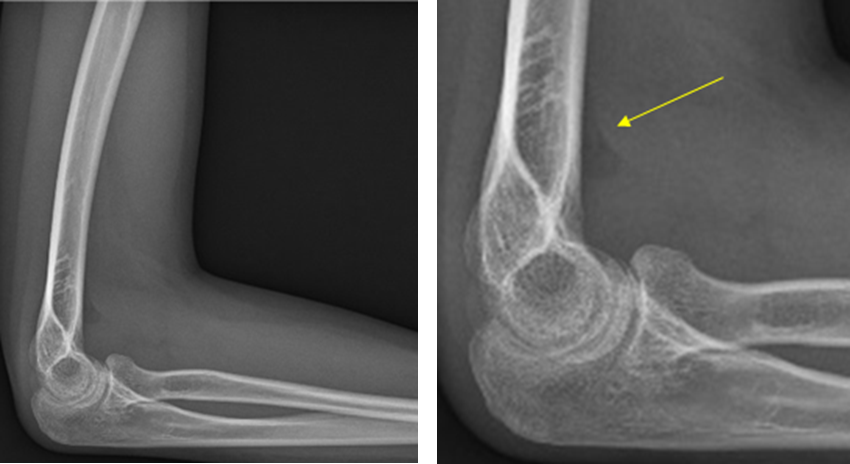

±×·¯¸é¼­ ½ÇÁ¦ ¹æ»ç¼± ÀåÄ¡·Î ÃÔ¿µÇÑ °á°ú¸¦ ¿¹·Î Á¦½ÃÇß´Ù.

À̵éÀº “X-ray¿¡¼­ º¸ÀÌ´Â »À¿¡´Â °ñÀý¼Ò°ßÀÌ º¸ÀÌÁö ¾ÊÁö¸¸ ¿À¸¥ÂÊ ¿µ»óÀÇ È­»ìÇ¥°¡ °¡¸®Å°´Â °ËÀº ºÎºÐÀº °ñÀý¿¡ ÀÇÇØ °üÀý¿¡ ¹°¿¡ Â÷¼­ Áö¹æÀ» µé¾î¿Ã·Á ¹ß»ýÇÑ °Í”À̶ó°í ¼³¸íÇß´Ù.

±×·¯¸é¼­ “X-ray ÆÇµ¶Àº »À»Ó¸¸ ¾Æ´Ï¶ó ¿¬Á¶Á÷¿¡¼­ º¸ÀÌ´Â ÀÌ·± ¼Ò°ßÀ» È®ÀÎÇÒ ÁÙ ¾Æ´Â ´É·ÂÀÌ ÇÊ¿äÇϸç, ÀÌ»óÀÌ ÀÖ´Ù¸é ¿øÀÎÀ» ¸íÈ®È÷ ¾Ë±â À§ÇØ Ãß°¡°Ë»ç ¿©ºÎ¸¦ °áÁ¤ÇØ¾ß ÇÑ´Ù”¸ç “¸¸¾à ÀÌ X-ray¸¦ Âï°íµµ Á¤»óÀ¸·Î ÆÇµ¶ÇÏ¿© Ãß°¡°Ë»ç¸¦ ½ÃÇàÇÏÁö ¾Ê¾Ò´Ù¸é À߸øµÈ Áø´ÜÀ» ³»¸° °Í”À̶ó°í °­Á¶Çß´Ù.